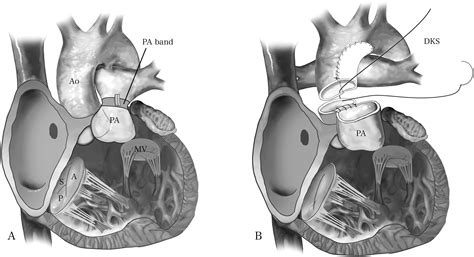

Because the anatomy of Double Inlet Left Ventricle cannot be "fixed" in a way that creates two fully functional pumping chambers, treatment focuses on "single-ventricle palliation." This involves a series of staged surgeries designed to reroute blood flow so that oxygen-poor blood travels to the lungs passively, bypassing the heart entirely, while the single ventricle focuses solely on pumping oxygen-rich blood to the body.

The standard surgical pathway generally includes three main procedures:

1. The Norwood Procedure (or shunt placement): Often performed in the first weeks of life to ensure adequate blood flow to the lungs or the body.

2. The Glenn Procedure (Bidirectional Glenn): Usually performed between 4 and 6 months of age, this connects the superior vena cava directly to the pulmonary arteries.

3. The Fontan Procedure: Typically performed between ages 2 and 5, this creates a final pathway for blood returning from the lower body to flow directly into the pulmonary arteries.